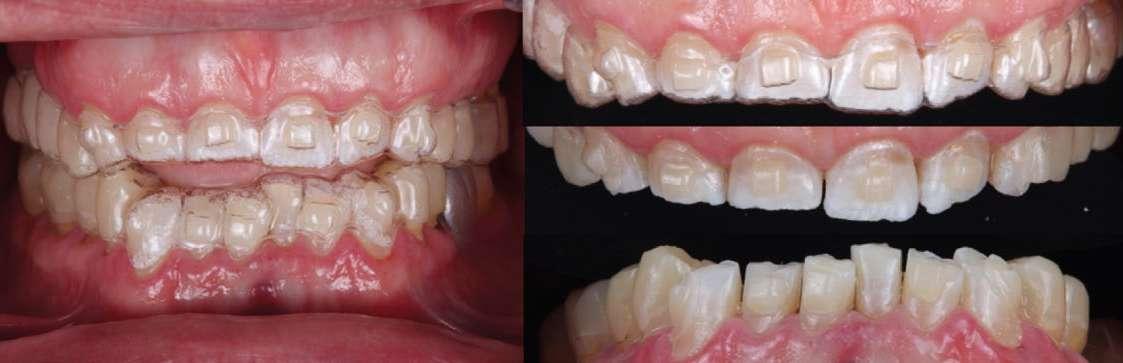

Presentación del caso

Paciente varón de 51 años que acudió a la Clínica Universitaria Odontológica (CUO) de la Universitat Internacional de Catalunya motivado por la necesidad de mejorar tanto su salud bucal como la estética de su sonrisa. El paciente manifestaba sensibilidad dental frecuente, especialmente al frío, episodios de incomodidad funcional durante la masticación y una marcada disconformidad con la apariencia estética de sus dientes. Entre sus principales expectativas destacó el deseo de obtener una rehabilitación integral que le proporcionara confort funcional y un resultado estético natural, siempre evitando procedimientos quirúrgicos o tratamientos excesivamente invasivos.

En la exploración clínica inicial se observaron signos compatibles con desgaste dental generalizado, pérdida de estructura dentaria a nivel incisal y oclusal, y presencia de restauraciones previas con

distintos grados de desajuste marginal. Se evidenció también una leve recesión gingival localizada y alteraciones en la alineación dentaria que afectaban a la estética de la sonrisa. El estado periodontal general era aceptable, con índices de placa y sangrado controlados, sin presencia de movilidad dentaria significativa.

Hallazgos clínicos iniciales

 Desgaste dental generalizado, compatible con erosión en palatinos de sector anterior superior y caras oclusales posteriores.

 Atrición en bordes incisales superiores e inferiores.

 Lesiones cervicales no cariosas (abrasiones por cepillado y abfracciones por sobrecarga oclusal).

 Presencia de puente metal-cerámica 1.5–1.7, con ausencia de piezas 1.6 y 3.6.

 Apiñamiento dental en incisivos inferiores y retroinclinación de incisivos superiores (torque negativo), diagnosticándose Clase II subdivisión 2.

Análisis estético

 Dientes cortos.

 Desgaste incisal irregular.

 Sonrisa alta con exposición gingival excesiva (“gummy smile”).

 Desbalance entre estética rosa y estética blanca.

 Canting anterosuperior.

Figura 1-3. Secuencia fotográfica extraoral inicial.

Figura 4-6. Análisis de la sonrisa del paciente.